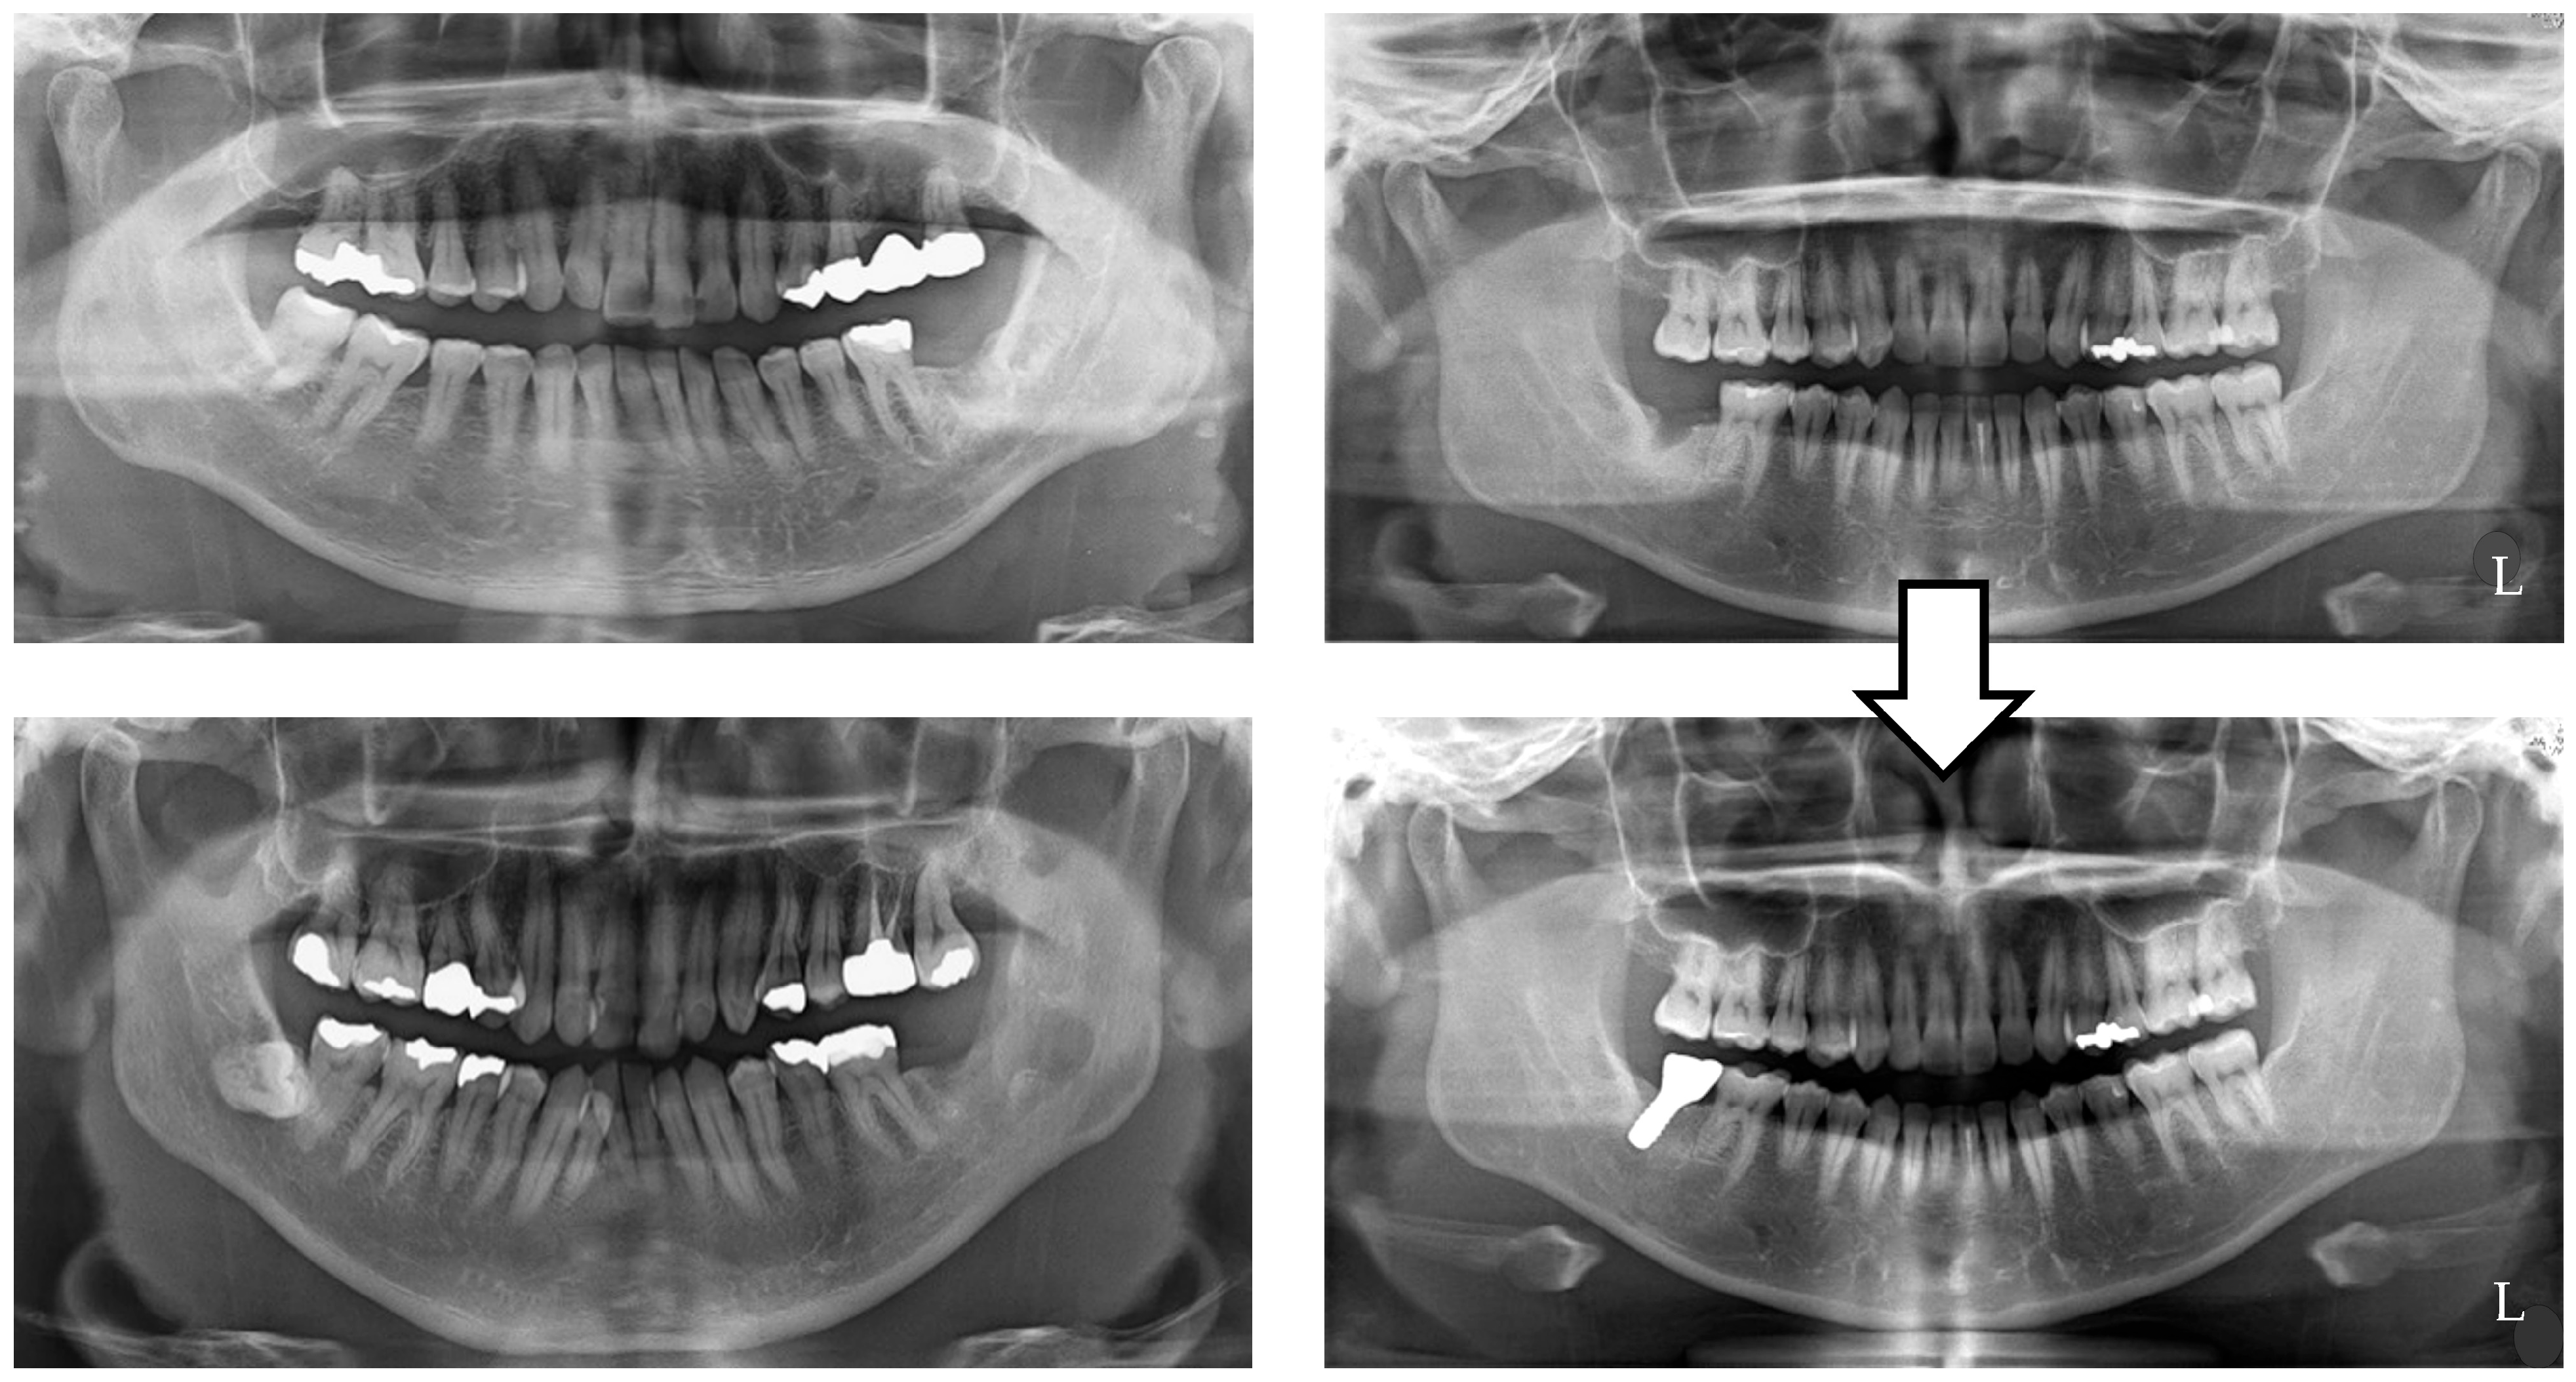

- Maximal occlusal force (Figure 2)

- Masticatory performance (Figure 3)

- Gonial angle (Figure 4)